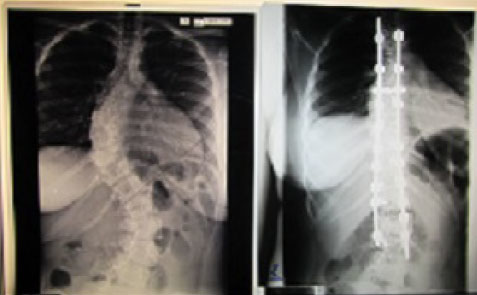

Three years ago, Sharena became the first young adult from the island of Dominica to benefit from scoliosis correction through a posterior spinal fusion. This surgery was provided to Sharena through World Pediatric Project (WPP), and supported through your donations to Globus Relief. World Pediatric Project works in Belize, Dominican Republic, Guatemala, Honduras, St. Vincent and the Grenadines, Panama, and in the Eastern Caribbean islands. Their mission is “to heal critically ill children and build healthcare capacity in the world.”

The positive impact of WPP’s work is best understood through the words of Sharena: “I am now a new, bold, enthusiastic individual living life to the fullest. Now I love myself and appreciate the way I look. Today my mission in life is to embark on a journey to help others in need. My life changing experience was made possible by WPP… I will be an advocate in my country, spreading the good news that no child should be denied medical care.”